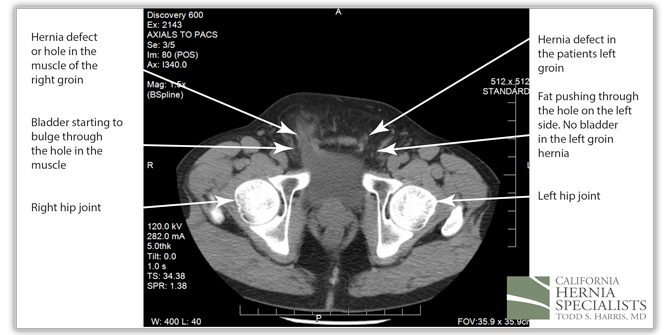

He was seen by his primary care physician in Arizona who ordered a CAT scan. The scan showed the images below including a large portion of his bladder in the right hernia. He also had a moderate sized fat containing hernia in the left groin.

However, in this CAT scan image, there is a noticeable hole in the lower muscle wall, and the start of an inguinal hernia both on the left and the right side of the groin.

The bladder can be seen squeezing through the hole in the muscles within the patients right groin (left side of the CAT scan image). On the patients left side (right side of the image), there is only fat pushing through the hernia defect.